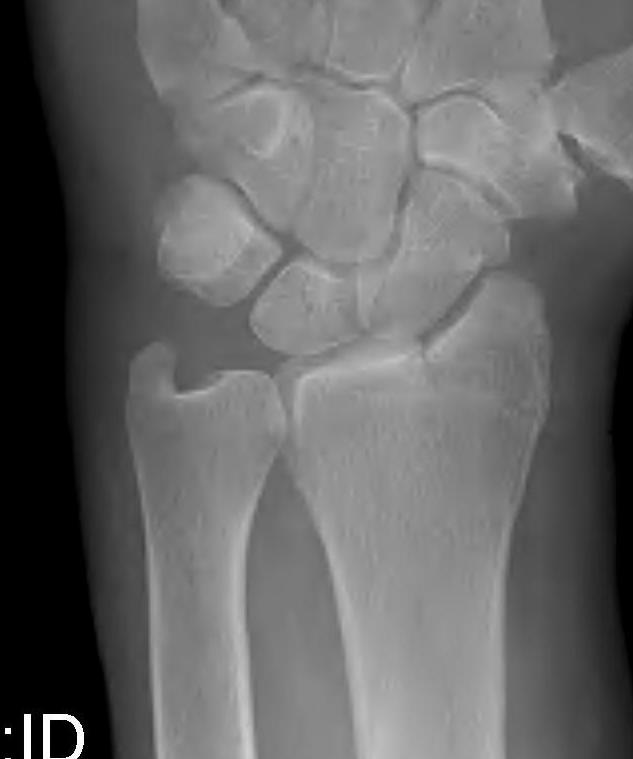

Radial angles

| Volar tilt mean 11° | Radial inclination mean 22° | Radius mean 11 mm longer than ulna |